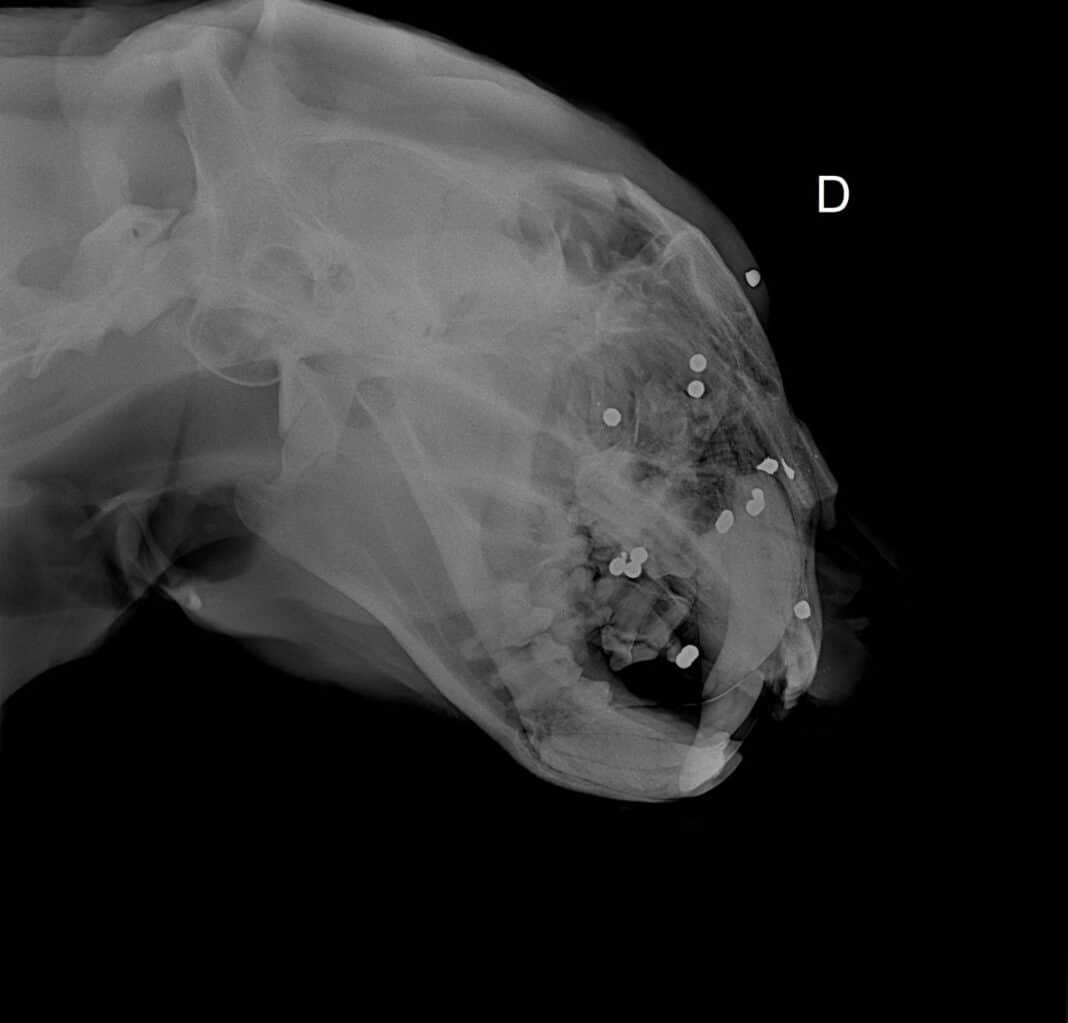

A onça-pintada macho resgatada ontem à noite em Marcelândia (165 quilômetros de Sinop), além de ter sido atropelada, também foi atingida por tiros. O animal foi encaminhado para uma clínica em Sorriso e passou por exames, que constatou a presença dos projéteis.

De acordo com o boletim médico, a onça foi avaliada pela veterinária Lilian Caldeira de Medeiros, que é responsável pelo atendimento de animais silvestres na região. Segundo o boletim, o estado do animal é considerado grave e há risco de morte. O felino segue internado em Sorriso e uma transferência não é descartada, mas será avaliada pela secretaria estadual de Meio Ambiente.